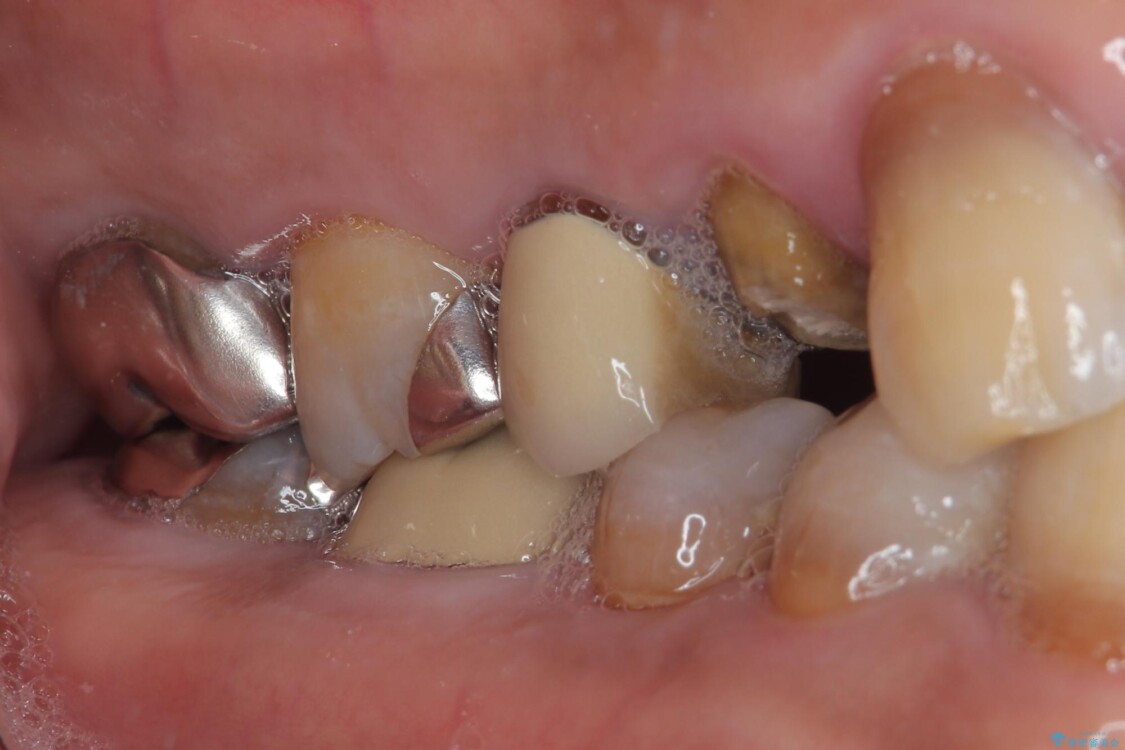

「以前治療した歯の被せものが外れてしまった」とのことで、右上の小臼歯の被せもの脱離を主訴に来院されました。

診察の結果、被せもの(クラウン)だけでなく、土台(コア)ごと外れてしまっている状態でした。根管治療済みの歯ではありますが、今回患者様のご希望により、根管治療の再治療は行わず、補綴処置のみを行う方針となりました。

治療前

• 自然な美しさと強度を両立!右上小臼歯の被せもの脱離に対する審美補綴治療 治療前画像